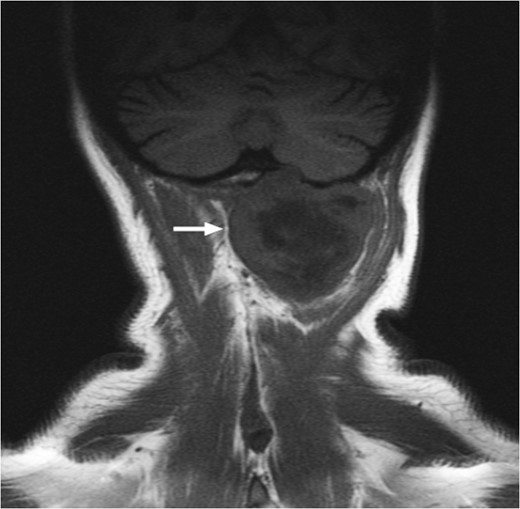

T1-weighted MRI showing the lesion eroding through the left basioccipital skull, impinging the dura overlying the left cerebellum.